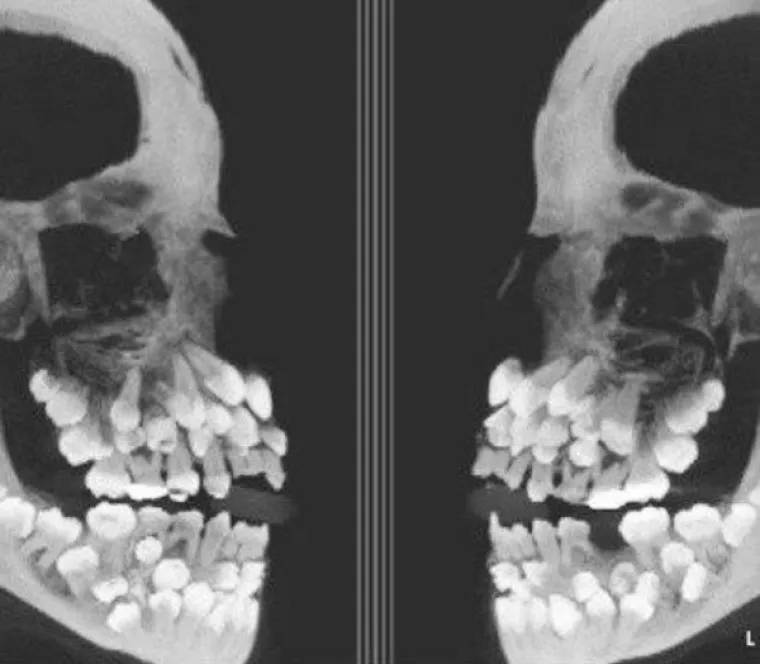

Rengen dječaka vrtićke dobi s  hiperdontijom